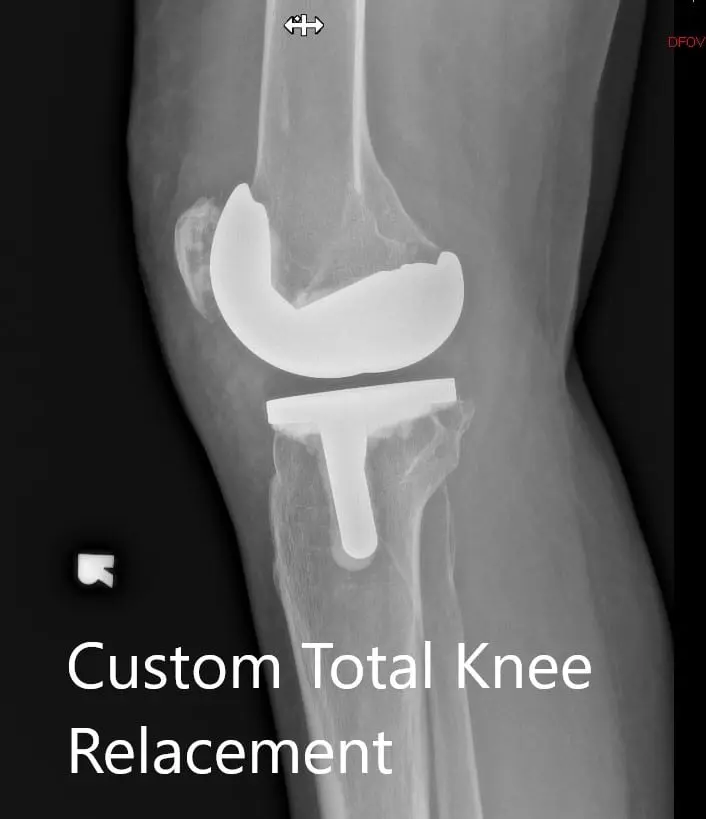

Postoperative X-ray showing the AP view of both knees

Postoperative X-ray showing the lateral view of the right and the left knee respectively

Postoperative X-ray showing the lateral view of the right and the left knee respectively - img 2